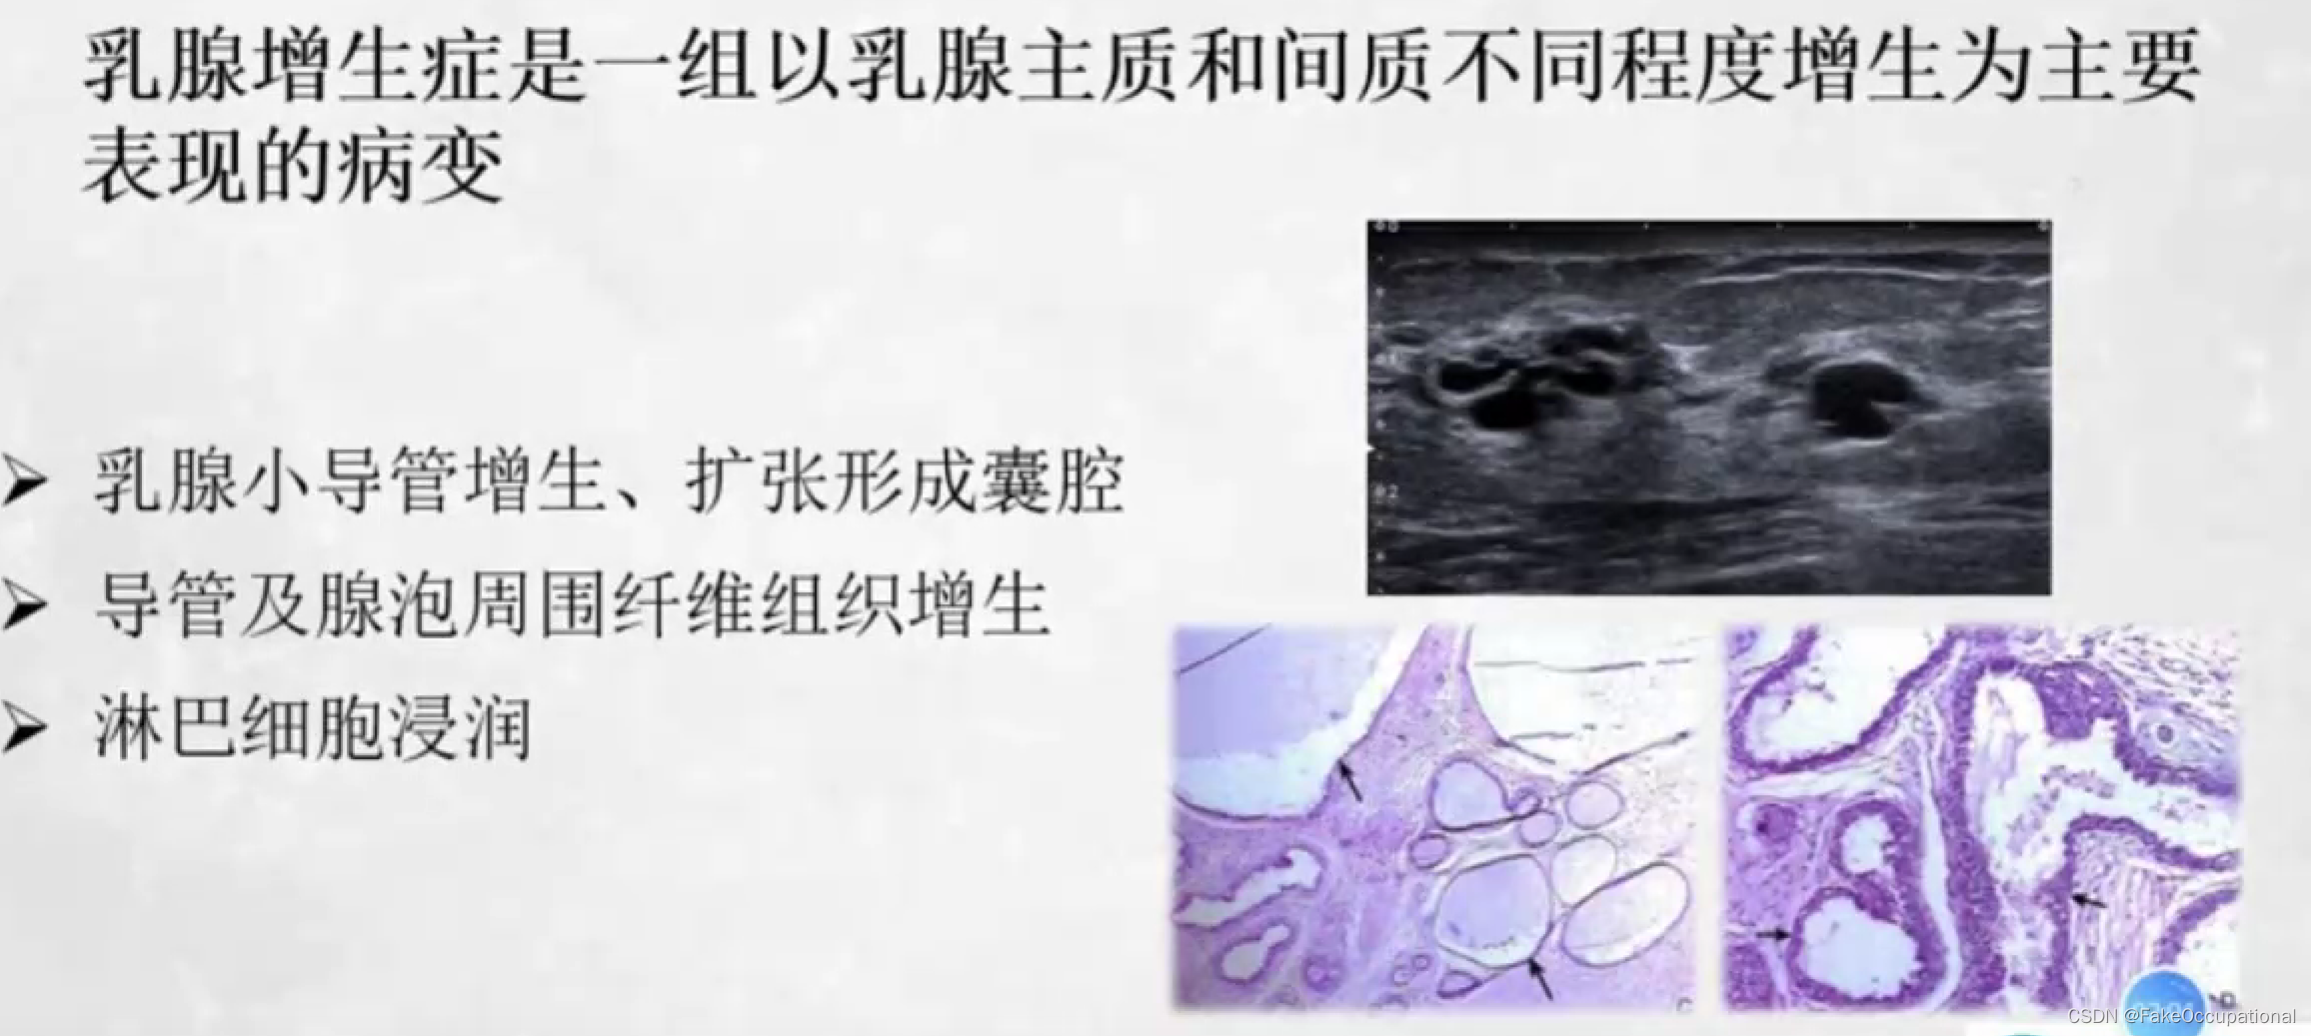

乳腺增生症

- 女性最常见的乳房疾病好发年龄为30一50岁与内分泌激素紊乱有关(尤其雌激素增高)

- 双侧乳腺周期性胀痛月经前3一4天疼痛加剧月经来潮后症状减轻

- 可触及多个大小不等的质韧结节多呈圆形或条索状

- 鉴别

乳腺瘤样增生需与乳腺纤维腺瘤、乳腺癌相鉴别。

可结合其他检查如:乳腺铂靶检查、乳腺核磁检查。

鉴别困难时,应定期随访或超声引导下穿刺活检。